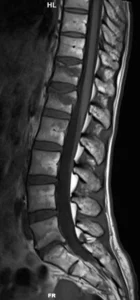

Resonancia Magnetica

RM sagital en secuencias T2 (1), T1 (2) y STIR (3). La RM permite establecer qué se trata de un trauma reciente por la presencia de edema óseo (hiperintenso en secuencias ponderadas en T2, hipointenso en T1). Es el método de elección para evaluar la médula espinal, el cono y las raíces nerviosas. Adicionalmente, muestra la patología degenerativa discal y vertebral.

Qué agrega la RM (y cuándo es clave):

- Confirma edema medular óseo (fractura aguda) y ayuda a diferenciar fracturas recientes vs crónicas.

- Valora lesión ligamentaria (complejo posterior) y tejidos blandos paravertebrales.

- Evalúa médula/conus/cauda y hematoma epidural si hay síntomas neurológicos.